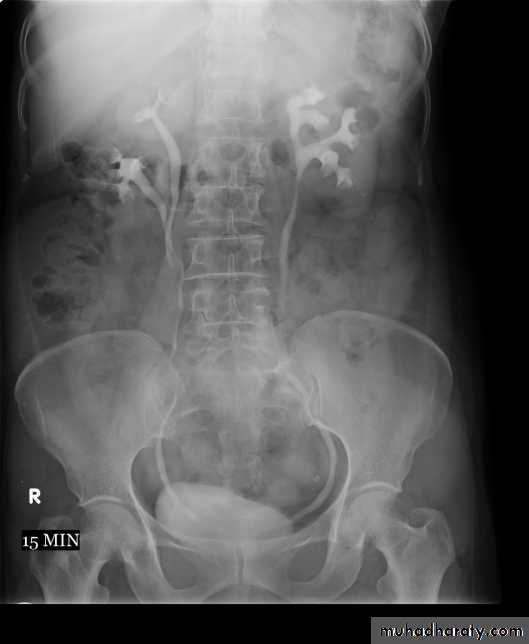

4. Full length film after release of compression .

-The normal renal pelvis and pelvi-ureteric junction are funnel shaped.-Ureters are seen only in part of their length on any one film due to obliteration by peristalsis.

Dilatation of pelvis and ureter may be due to:

-Obstruction (by stone , tumors or external compression).-secondary to vesico-ureteric reflux